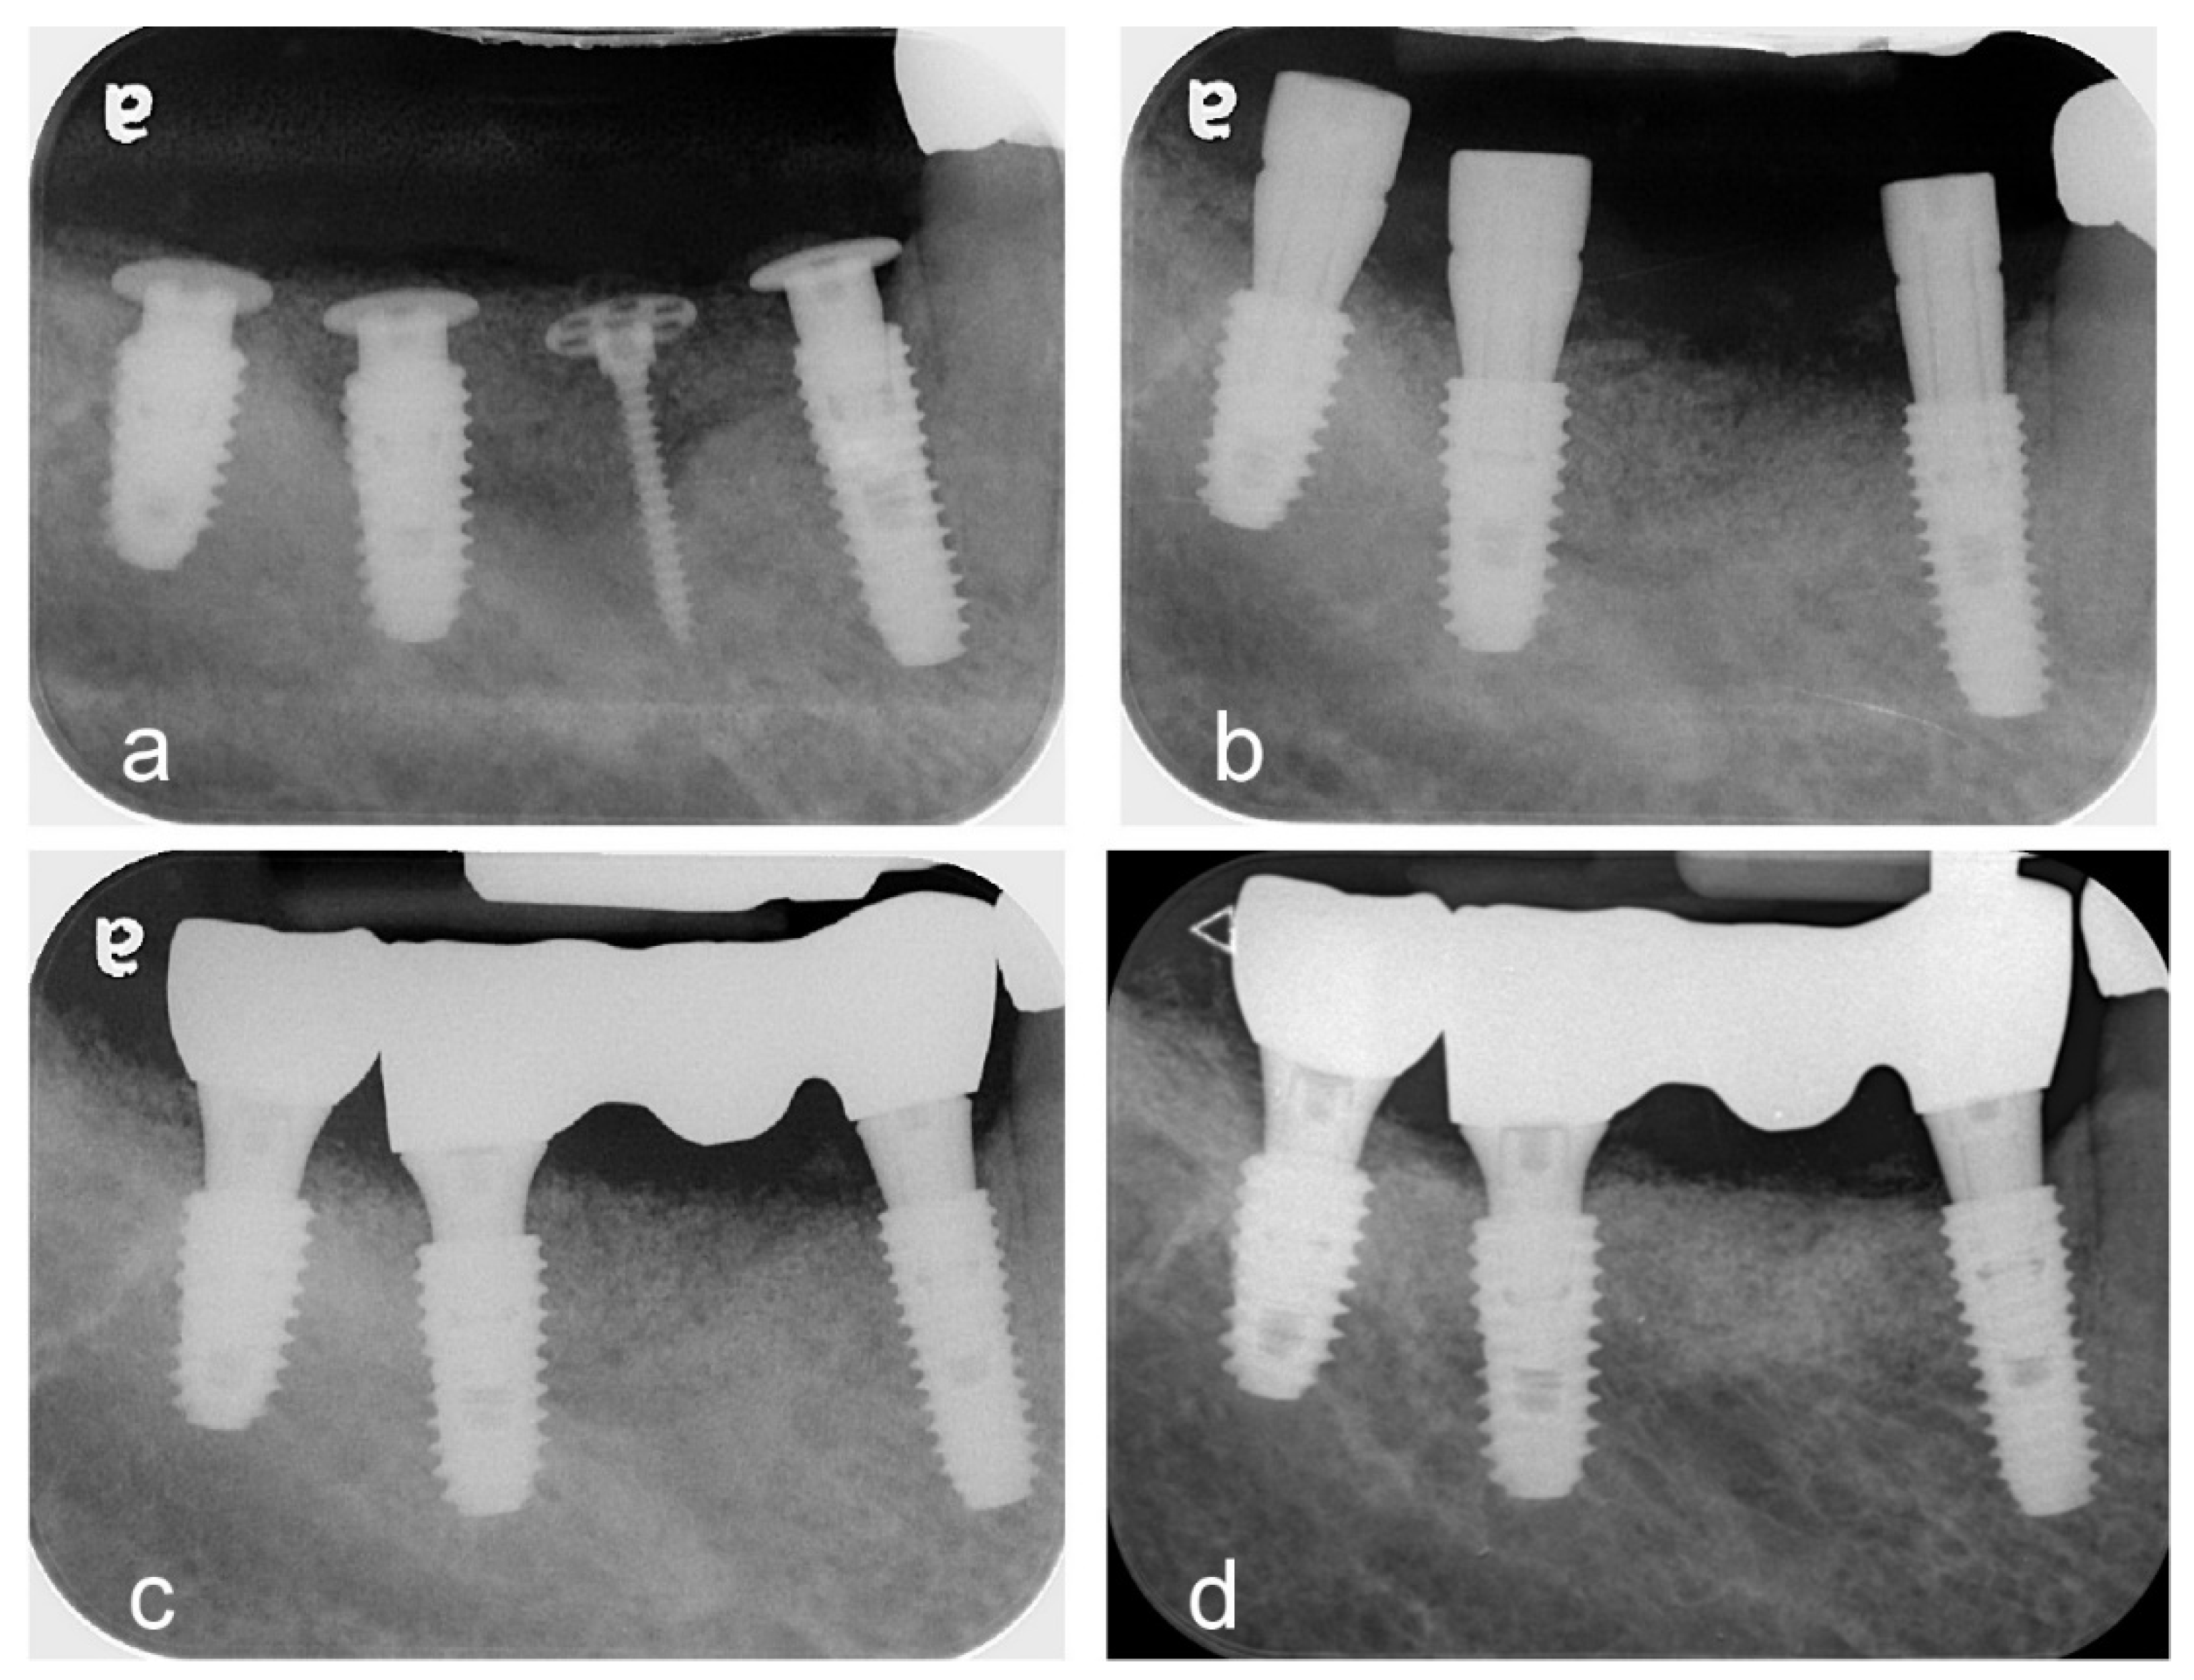

- Woo, R.H.; Kim, H.G.; Kim, G.; Park, W.E.; Sohn, D.S. Simplified 3-dimensional ridge augmentation using a tenting abutment. Adv Dent & Oral Health 2020, 12, 185–205. [Google Scholar]

- Woo, R.H.; Kim, H.G.; Kim, G.; Park, W.; Sohn, D. Simplified 3-Dimensional ridge augmentation using a tenting abutment. Adv Dent Oral Health 2020, 12, 185–205. [Google Scholar]

- Sohn, D.S. Reconstruction of three-dimensional alveolar ridge defects utilizing screws and implant abutments for the tent-pole grafting` techniques. In Tolstunov L, ed. Essential techniques of alveolar bone augmentation in implant dentistry, 2nd ed.; Wiley Blackwell: 2023; 404-418.

- Sohn, D.S.; Lui, A.; Choi, H. Utilization of Tenting Pole Abutments for the Reconstruction of Severely Resorbed Alveolar Bone: Technical Considerations and Case Series Reports. J. Clin. Med. 2024, 13, 1156. [Google Scholar] [CrossRef] [PubMed] [PubMed Central]